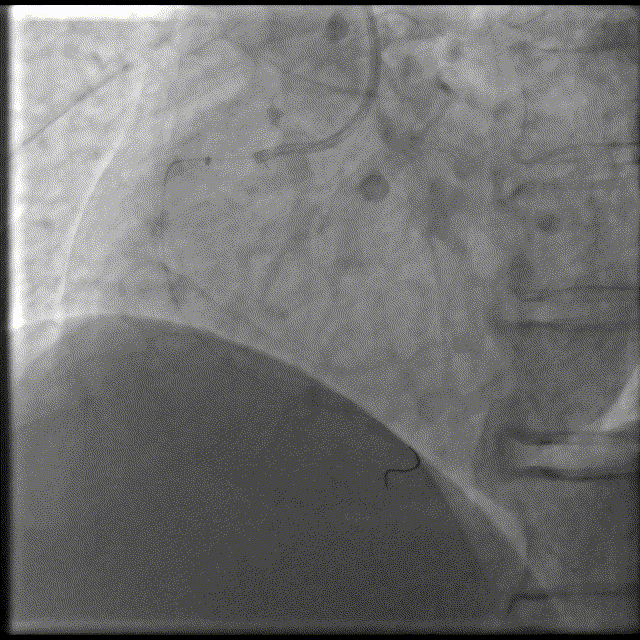

头位造影:RCA近中段钙化迂曲,第二转折处中度狭窄。

2.75x28mm支架,不能通过近中段。

换用6F GC,Telescope™导引延长导管辅助下,2.5x15mm,14-16atm。